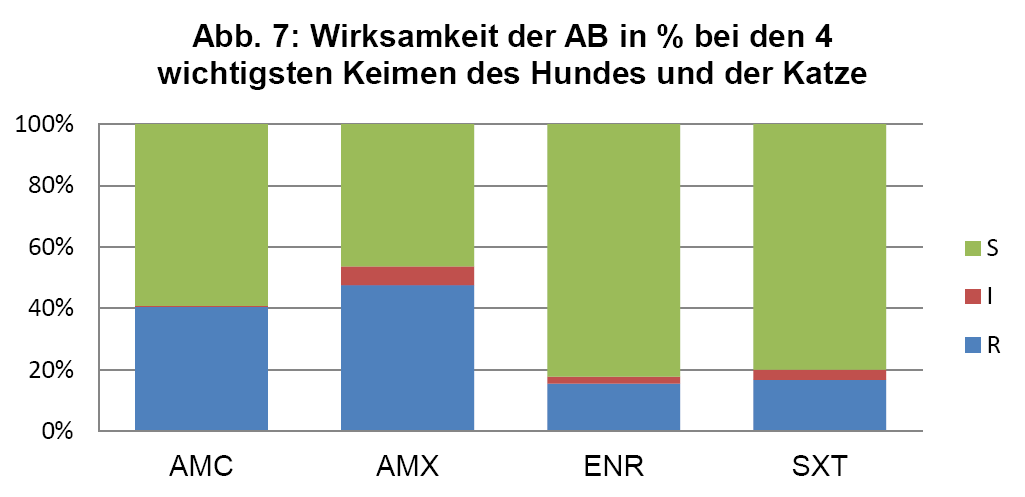

- Abb. 7: Wirksamkeit der AB in % bei den 4 wichtigsten Keimen des Hundes und der Katze

Um einen besseren Überblick über die mögliche Wirksamkeit einer Ersttherapie gemäß ISCAID Richtlinien zu geben, sind in Abb. 7 die jeweils vier wichtigsten Keime bei Hund und Katze gegen die häufig als Ersttherapie eingesetzten Wirkstoffe zusammengefasst.

Für die Ersttherapie werden nach ISCAID Richtlinien AMX und SXT vorgeschlagen, wobei AMX der Vorzug gegeben wird. In vielen europäischen Ländern ist AMX sehr gut wirksam gegen E. coli. Dies ist offensichtlich bei uns nicht der Fall (s. Abb. 4). Bei unklarer Keimzusammensetzung wäre daher SXT nach unserer Datenlage für die Ersttherapie der Vorzug zu geben. Auf ENR sollte zunächst aus den oben genannten Gründen verzichtet werden. Es wird noch als Reserveantibiotikum für wirklich schwierige Infektionen benötigt. Wenn im Harnsediment eine Unterscheidung in Kokken und Stäbchen erfolgt, kann man bei Vorliegen von Kokken gut mit AMX als Ersttherapie arbeiten (s. Abb. 5 + 6). Es muss bedacht werden, dass die uns vorliegenden Daten die eigentliche Resistenzlage zu hoch wiedergeben könnten, da häufig erst bei Therapieversagen eine BU eingeleitet wird. Somit könnte die Resistenzlage für AMX in der Praxis besser sein, als hier dargestellt. Darüber hinaus reichert sich AMX im Urin stark an.